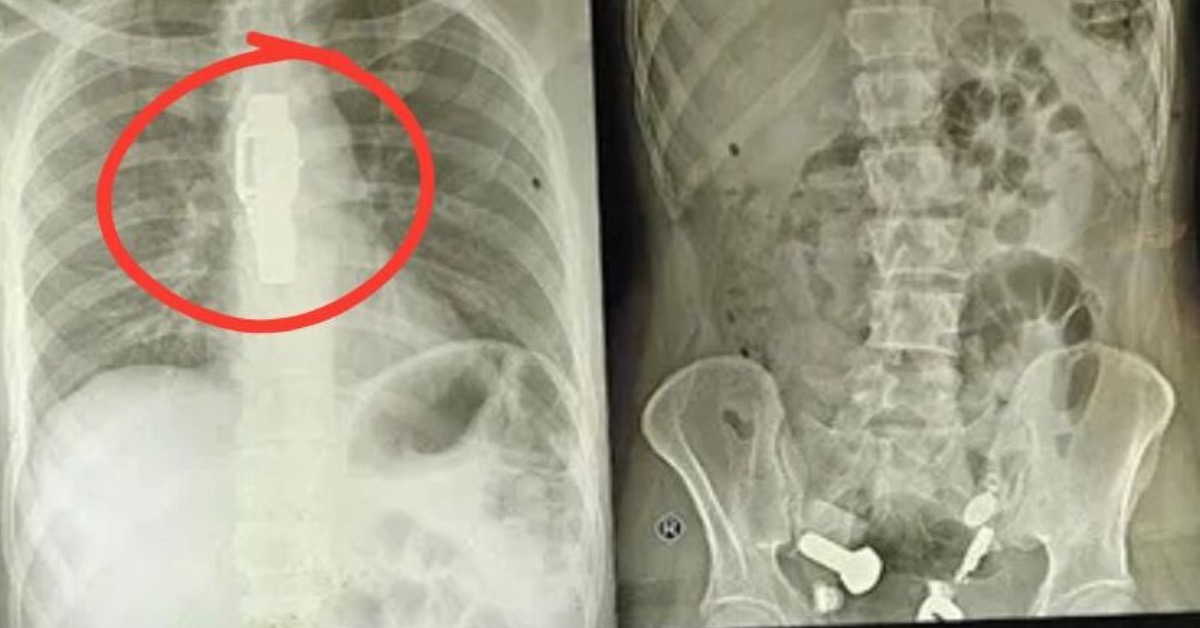

印度齋浦爾34歲男子連日腹痛就醫,竟被發現手錶卡食道、腸內堆滿鐵片螺絲。(圖/翻攝自X)

印度拉賈斯坦邦首府齋浦爾一名34歲男子,因連日嘔吐與劇烈腹痛被緊急送醫,醫療團隊檢查時驚見「手錶」卡在食道,腸道內更堆滿鐵片、螺帽與螺絲等硬物。院方隨即動員外科與消化科聯手,歷時約3小時手術,透過腹部小切口與內視鏡輔助,將體內異物一次清出;患者術後生命徵象穩定,留院觀察。醫院研判,男子因精神疾病引發幻覺與衝動性行為,進而反覆吞食異物。

據《The Times of India》報導,院方指出男子10月9日入院時已無法進食喝水,初步以內視鏡評估卻「一路受阻」,影像學檢查才發現食道被整只手錶卡住。更令人錯愕的是,消化道其他部位還散落多種金屬物與石塊,包括鐵片、螺絲、螺帽及大理石塊。手術過程中,醫師必須兼顧出血風險、穿孔風險與金屬邊緣造成的二度損傷,團隊以分段夾取與小切口輔助方式,最終安全取出所有異物。